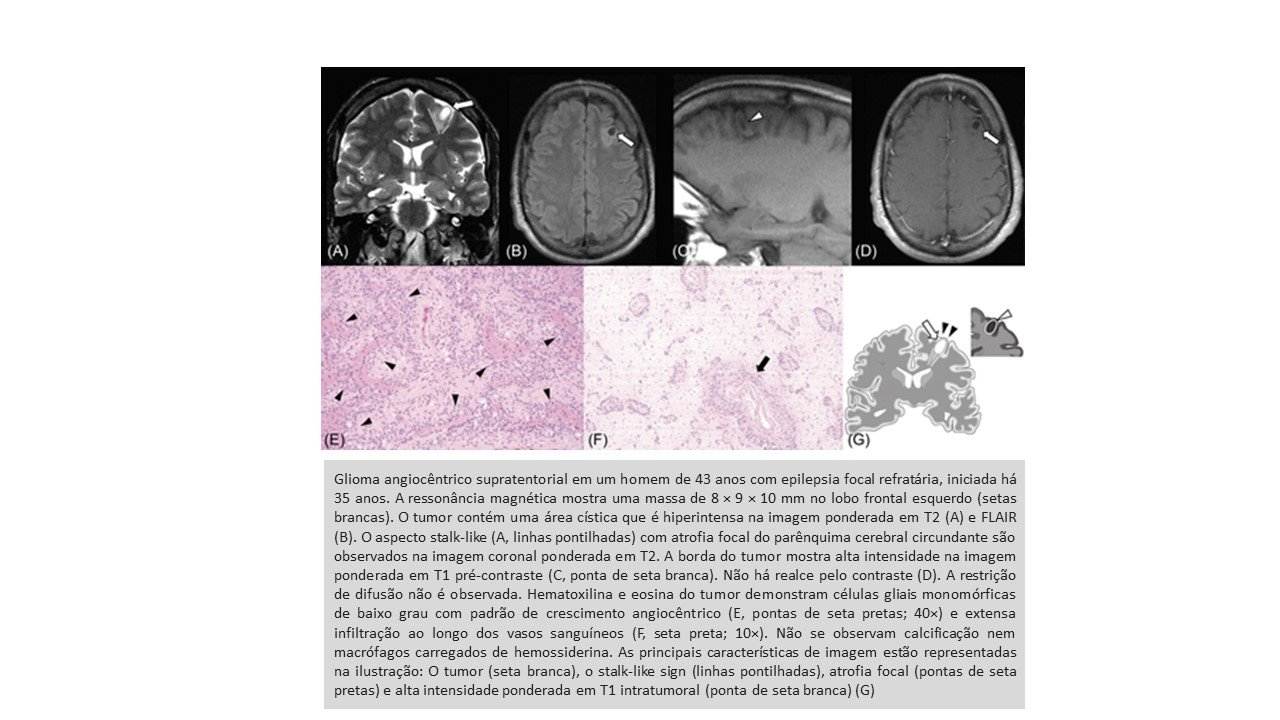

Radiologicamente, duas características dos GAs foram relatadas – alta intensidade na imagem ponderada em T1 (T1WI) e um aspecto stalk-like visto no T2 que se estende para o ventrículo . No entanto, a frequência desses achados na RM é desconhecida, e vários autores relataram casos sem essas características “patognomônicas”.

A maioria dos pacientes tinha história de convulsão/epilepsia. Foi encontrado incidência das características de neuroimagem, incluindo área de alta intensidade intratumoral em T1WI (46%), sinal semelhante a pedúnculo (20%) e atrofia do parênquima cerebral circundante (28%). Além disso, várias correlações clínicas e de imagem não identificadas foram encontradas: houve fortes relações entre o tempo de história de crise/epilepsia e a presença dos achados de RM acima mencionados; a idade do diagnóstico foi significativamente menor em pacientes com GA de tronco encefálico do que naqueles supratentoriais.

Características de neuroimagem dos GAs, como alta intensidade de sinal em T1WI, ausência de realce, localização superficial e stalk-like sign em T2WI/FLAIR, foram observadas em estudos anteriores. Neste estudo, foi demonstrado a frequência de cada achado de neuroimagem. Por exemplo, verificou-se que o conhecido stalk-like sign não era frequente. O realce do contraste foi observado em mais de um quarto dos pacientes, embora os GAs sejam geralmente considerados sem realce pelo contraste.

As áreas de alta intensidade intratumorais em T1WI foram significativamente mais comuns em pacientes com atrofia regional e stalk-like sign. A duração da história de convulsão/epilepsia foi significativamente maior em pacientes com áreas intratumorais T1WI de alta intensidade, sinais semelhantes a pedúnculos e atrofia regional. Esses achados sugerem que áreas de alta intensidade de T1WI dos GAs podem refletir algum processo crônico. Em relação ao stalk-like sign, os autores assumiram que reflete várias patologias diferentes, como infiltração tumoral junto com os vasos que se estendem da superfície do cérebro em direção ao ventrículo, gliose peritumoral causada pela existência de tumor de longa data ou estresse oxidativo induzido por convulsão, e DCF coexistentes, como é o caso do tumor neuroepitelial polimorfo de baixo grau do jovem. De fato, a coexistência de GA e FCD foi patologicamente comprovada em três casos, incluindo dois casos com stalk-like sign. A FCD pode causar convulsão/epilepsia de longa data e, inversamente, uma longa história de convulsão/epilepsia pode causar atrofia regional e degeneração do parênquima cerebral ao redor do tumor. A presença de longa data do GA também explica a alta incidência de atrofia cerebral induzida por convulsão/epilepsia associada ao tumor e extensão do tumor semelhante a stalk-like.

Os GAs são gliomas epileptogênicos de baixo grau que ocorrem frequentemente em regiões supratentoriais superficiais em pacientes com menos de 20 anos de idade. Os GAs de tronco encefálico foram observados em pacientes mais jovens e não causaram convulsões ou epilepsia. Achados de imagem característicos dos GAs (ou seja, áreas de hipersinal intratumorais emT1WI, stalk-like sign e atrofia do parênquima cerebral circundante) podem ser induzidos pela natureza indolente dos GAs e convulsão/epilepsia de longa data associada e/ou DCF e gliose coexistentes.